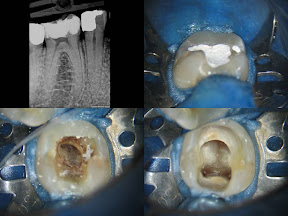

Tratamento endodontico dente - 46 - Canais Mesiais longos